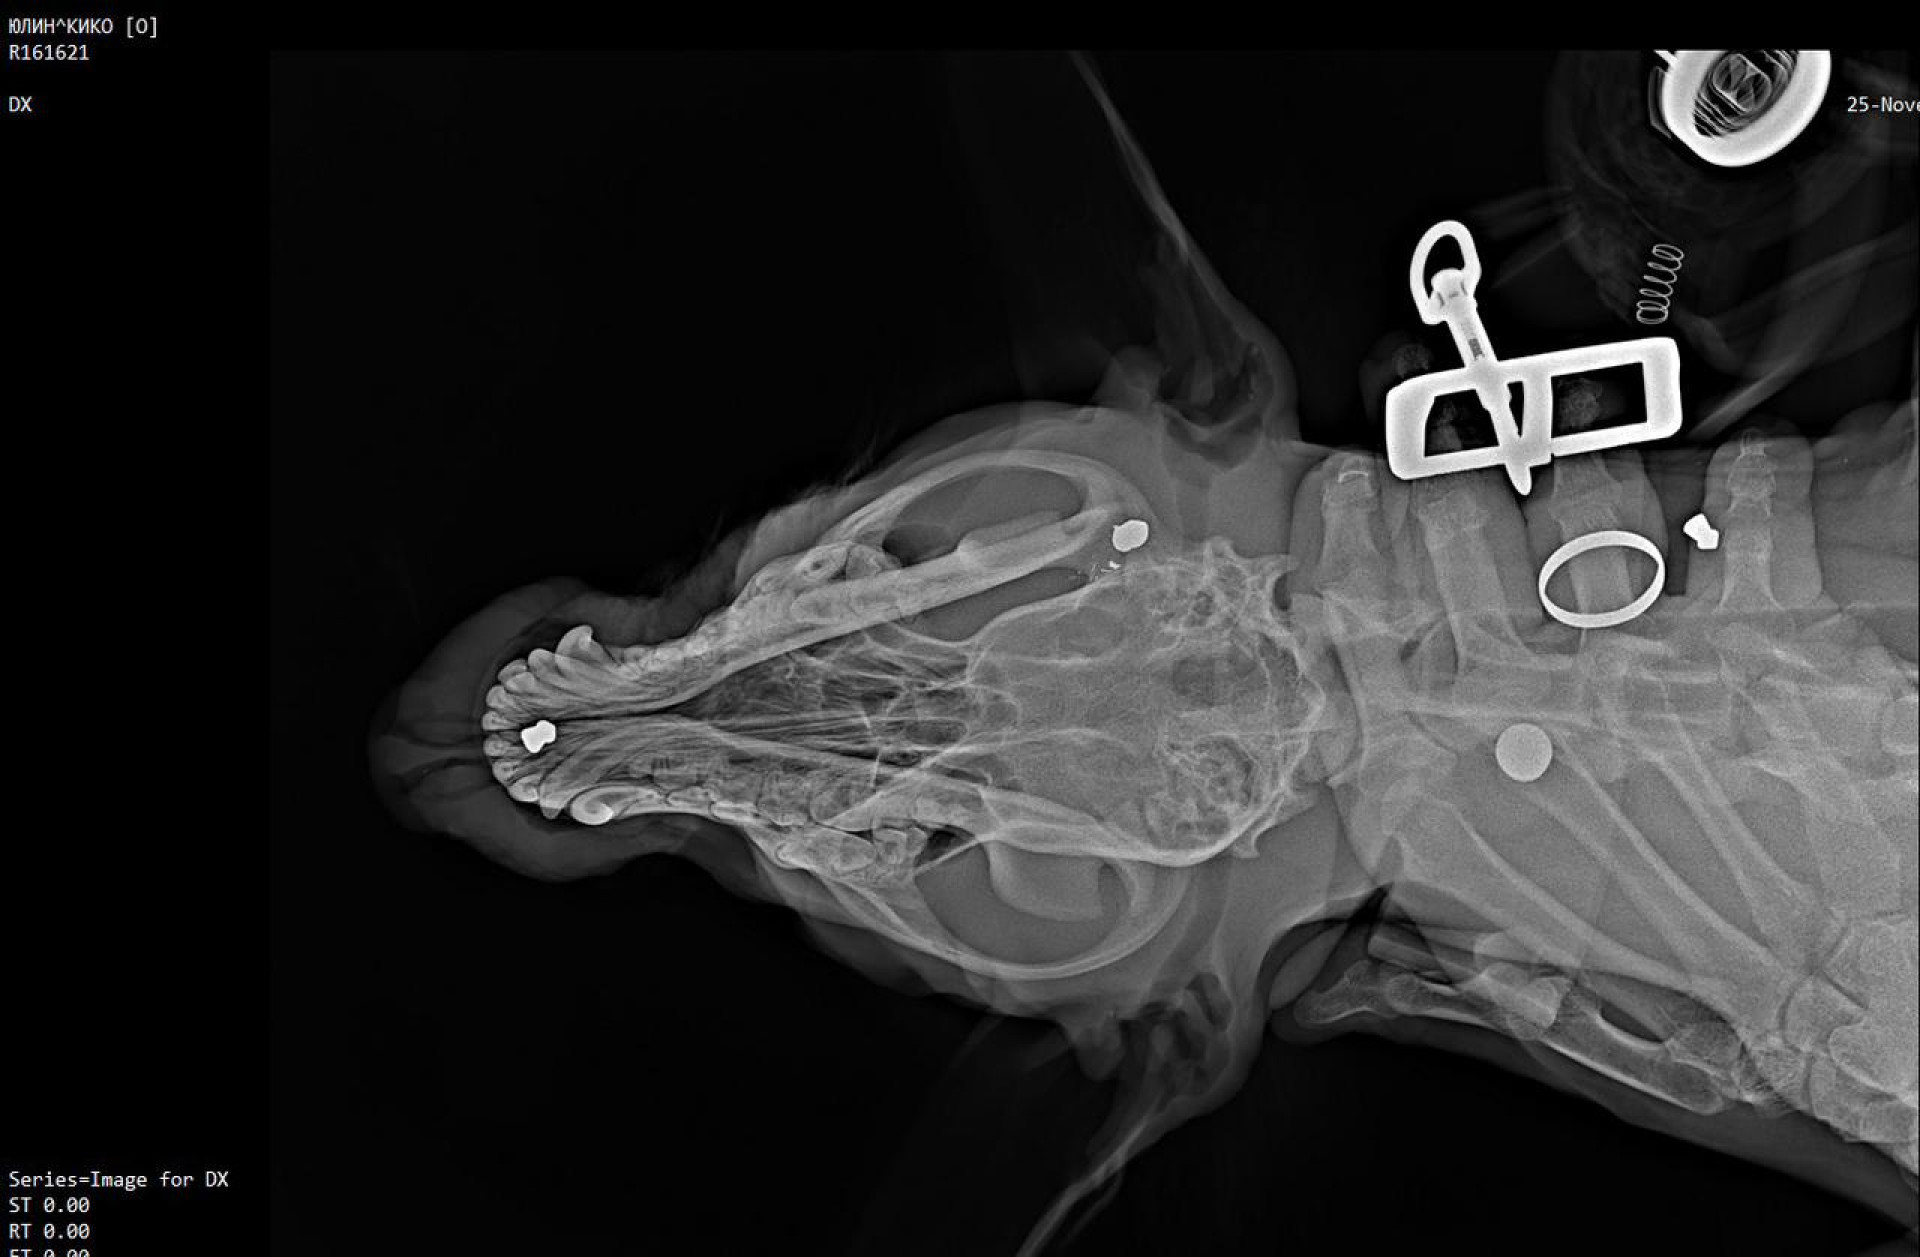

"В 10 утра прогревали машину, когда увидели с супругом, как одна из уличных собак с воем, истекая кровью, пробежала мимо нас. Мы прошли в ту сторону, откуда она прибежала, и увидели соседа с ружьём, который стрелял по псам. Он выстрелил в нашего питомца, пуля попала ему в позвоночник, задние лапы отказали. Еще одной собаки пуля попала в глаз. Мы отвезли нашего пса и уличного к ветеринару, выяснилось, что у нашей повреждён спинной мозг, она навсегда останется инвалидом, а у дворовой в голове обнаружено три дроби", — рассказала жительница села Амина (имя изменено).

Фото предоставлено Аминой